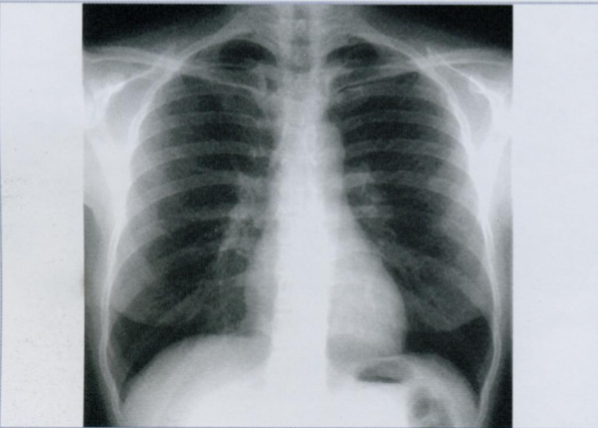

4

Q

Как расположены ребра на Rx грудной клетки?

Как выглядят верхушки легких на снимке?

Обратите внимание на верхушки легких. Что Вы ещё видите на снимке?

Обычно Rx выполняются при глубоком вдохе, когда в легком находится максимально возможное количество воздуха, и потому оно имеет наименьшую плотность. При корректно выполненом снимке на вдохе должны считаться 10 ребер по задней поверхности (или шесть по передней).

A

Задние сегменты ребер расположены горизонтально, передние проходят косо кпереди и книзу.

Верхушки легких, которые прикрыты первым ребром, могут выглядеть как участки сверхпрозрачности. Это обман зрения от перепада контрастности между ребром и верхушкой легкого.

Не перепутайте с буллой/пневмотораксом.

Rx грудной клетки на вдохе с признаками левостороннего пневмоторакса.

Normalmente las radiografías se toman en inspiración profunda, de manera que el pulmón tiene la mayor cantidad de aire posible y por tanto la menor densidad. En una placa correctamente inspirada deben poder contarse 10 costillas por su parte posterior (o seis por la anterior).